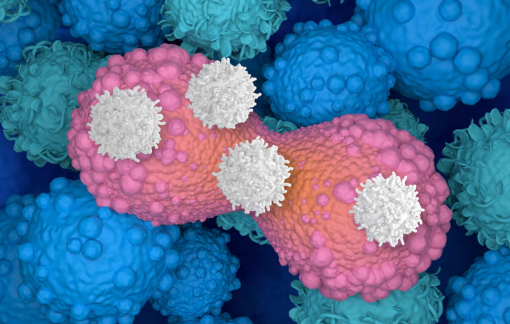

Một loại thuốc thử nghiệm mới mang đến hy vọng cho bệnh nhân ung thư sau khi cho thấy khả năng thu nhỏ khối u hiệu quả.

Một loại thuốc tiêm điều trị ung thư đang mang đến hy vọng mới cho những bệnh nhân đã không còn đáp ứng với các phương pháp điều trị thông thường.

Các nhà khoa học vừa tìm ra phương pháp tiêu diệt các tế bào "xác sống" gây ung thư và lão hóa, mở ra hy vọng cho các liệu pháp mới.